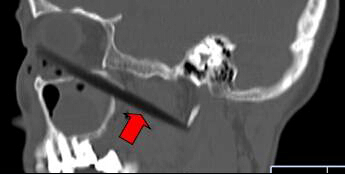

CT顯示筷子還插在腦部

取出的斷筷有9厘米

上周三,62歲的依姆林瓊(化名)在南平家中,有人在揮舞筷子時,將筷子從她右眼眶插入,鼻孔瞬間出血。家人心急,用老虎鉗將筷子外端夾斷,剩下半截筷子嵌在頭面部,之后將其緊急送到福建醫(yī)科大學(xué)附一醫(yī)院。經(jīng)過1個多小時的緊急手術(shù),9厘米長的斷筷被取出,由于筷子未插中眼球,患者眼睛未受影響。附一醫(yī)院耳鼻喉科副主任醫(yī)師張暉萍提醒,千萬不可自行強拔已插入體內(nèi)的物體。傷者被送到附一醫(yī)院時,醫(yī)生幾乎都看不到筷子了。在醫(yī)生的詢問下,家屬這才說,當(dāng)時,他們一心急,用老虎鉗將筷子外端夾斷。這下棘手了。若筷子是完整的還容易拔出,這下完全埋在眼眶下,可怎么取出?影像學(xué)檢查顯示,筷子就靠近視神經(jīng)管、頜內(nèi)血管分支,末端位于頸部大動脈的前方。手術(shù)稍有不慎,就可能大出血。為了取出斷筷,附一醫(yī)院耳鼻喉科、頜面外科、眼科、影像科馬上聯(lián)合會診,擬定了三套手術(shù)方案。第一方案,從插入口直接拔;第二方案,從鼻腔取;第三方案,鋸開眼眶取斷筷。最終,大家選擇了第一方案,因為創(chuàng)傷最小,由耳鼻咽喉科張暉萍副主任醫(yī)師和眼科朱學(xué)軍主任醫(yī)師聯(lián)合急診手術(shù)。醫(yī)生們先從眼眶內(nèi)切開傷口1厘米,才看到筷子斷端,順著原先插入口,在鼻窺鏡的幫助下,邊夾邊推,將筷子順利取出。取出的竹筷長達9cm,周圍有大量膿液。經(jīng)過多日抗感染治療,前日,老人才出院。